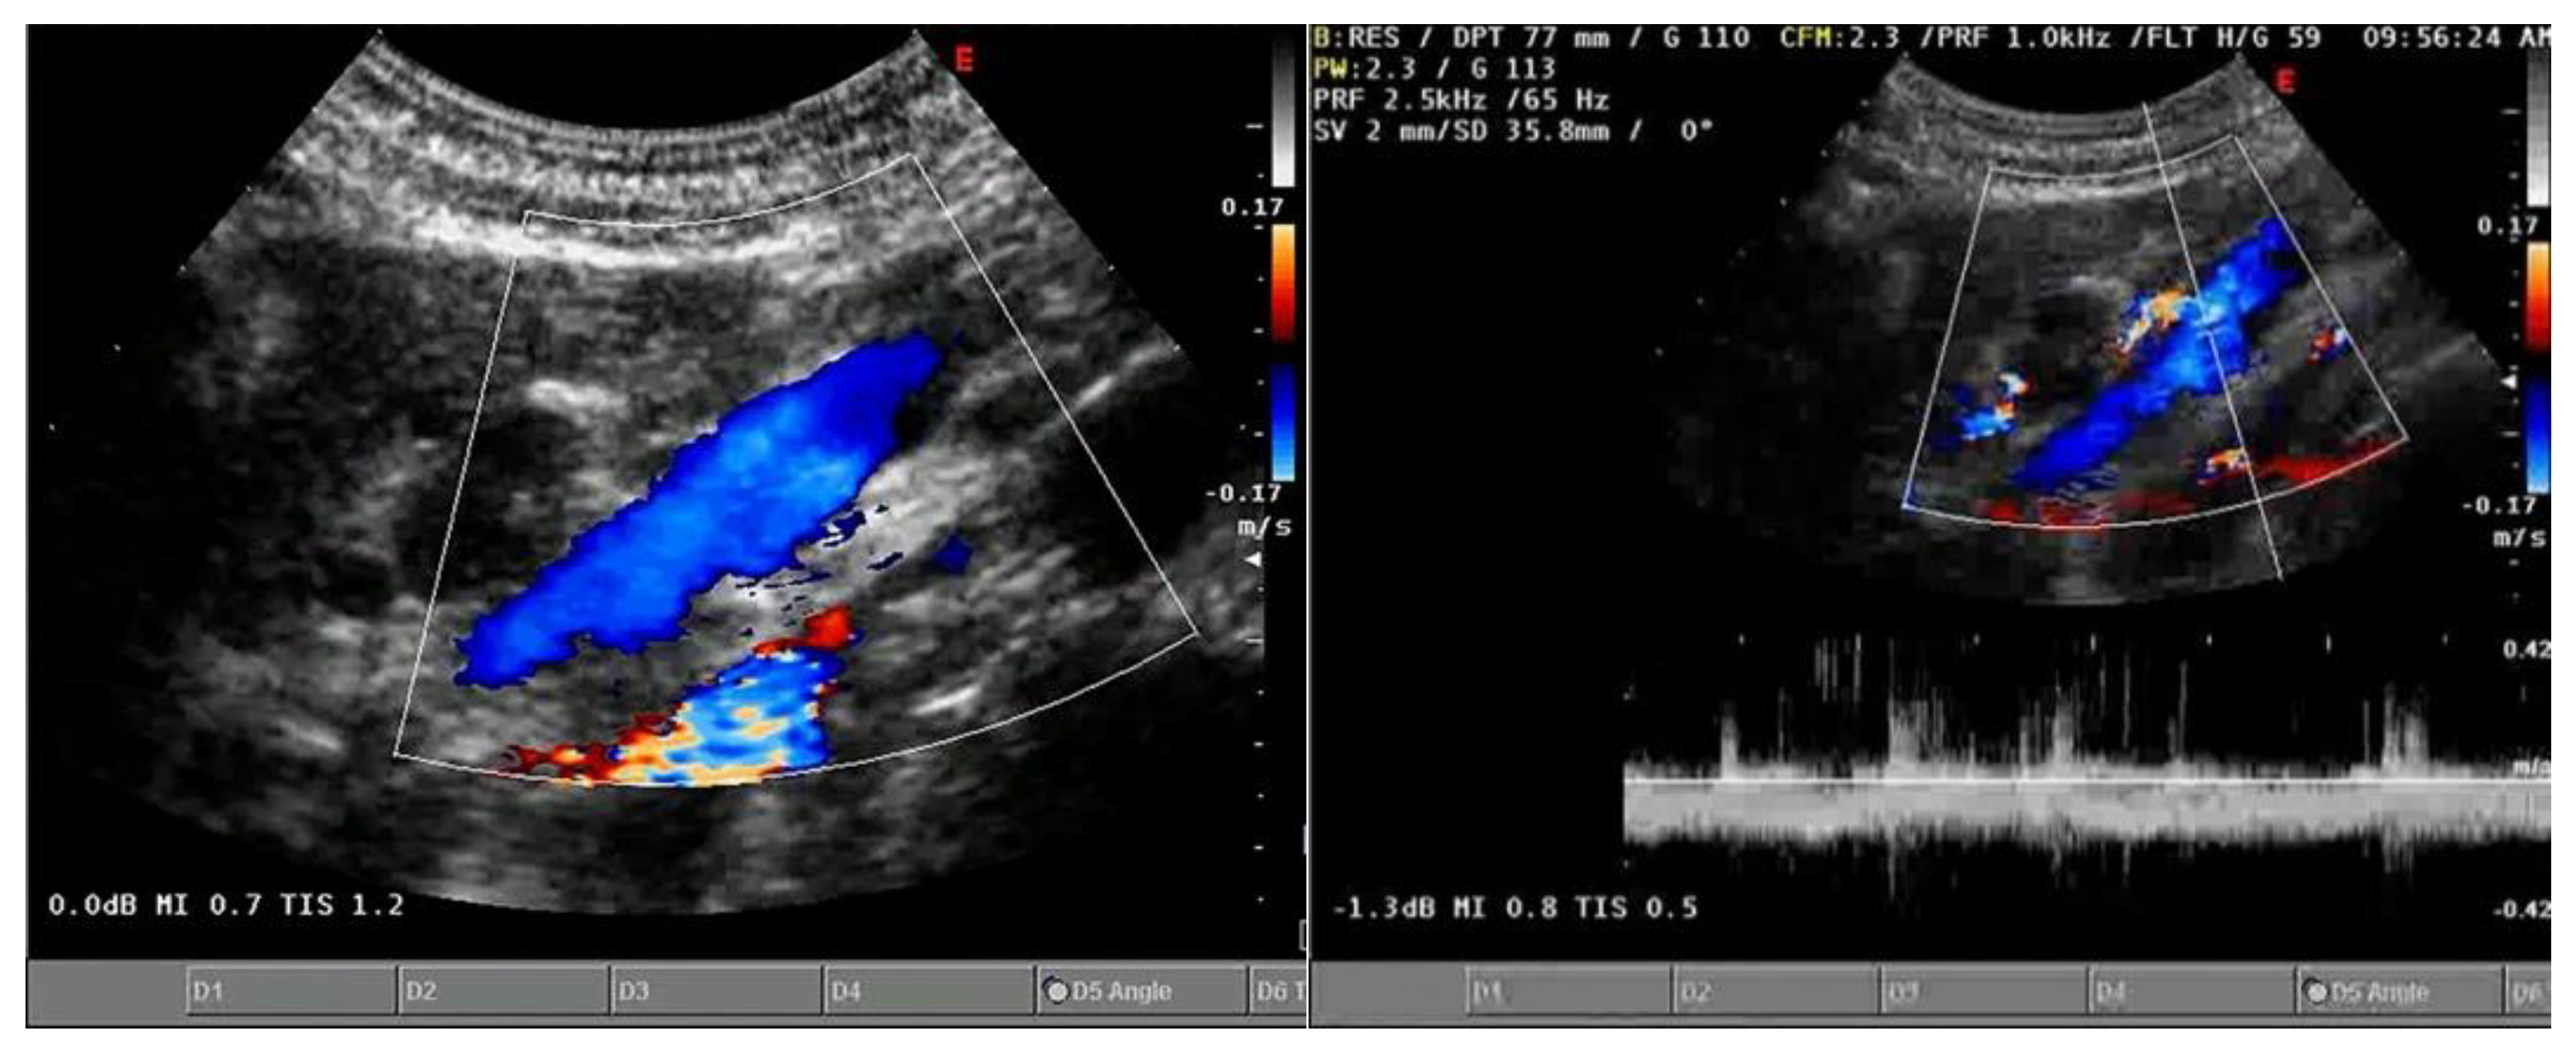

3.1.2. Ecocolordoppler and Spectral Velocity Variations:

PORTAL VEIN:

- Hosoki, T.; Arisawa, J.; Marukawa, T.; Tokunaga, K.; Kuroda, C.; Kozuka, T.; Nakano, S. Portal blood flow in congestive heart failure: pulsed duplex sonographic findings. Radiology 1990, 174, 733-736. [CrossRef]

- Abu-Yousef, M.M.; Milam, S.G.; Farner, R.M. Pulsatile portal vein flow: a sign of tricuspid regurgitation on duplex Doppler sonography. AJR Am J Roentgenol 1990, 155, 785-788. [CrossRef]

- Gallix, B.P.; Taourel, P.; Dauzat, M.; Bruel, J.M.; Lafortune, M. Flow pulsatility in the portal venous system: a study of Doppler sonography in healthy adults. AJR Am J Roentgenol 1997, 169, 141-144. [CrossRef]

- Rengo, C.; Brevetti, G.; Sorrentino, G.; D'Amato, T.; Imparato, M.; Vitale, D.F.; Acanfora, D.; Rengo, F. Portal vein pulsatility ratio provides a measure of right heart function in chronic heart failure. Ultrasound Med Biol 1998, 24, 327-332. [CrossRef]

- Goncalvesova, E.; Lesny, P.; Luknar, M.; Solik, P.; Varga, I. Changes of portal flow in heart failure patients with liver congestion. Bratislavske lekarske listy 2010, 111, 635-639.

- Catalano, D.; Caruso, G.; DiFazzio, S.; Carpinteri, G.; Scalisi, N.; Trovato, G.M. Portal vein pulsatility ratio and heart failure. J Clin Ultrasound 1998, 26, 27-31. [CrossRef]

- Deschamps, J.; Denault, A.; Galarza, L.; Rola, P.; Ledoux-Hutchinson, L.; Huard, K.; Gebhard, C.E.; Calderone, A.; Canty, D.; Beaubien-Souligny, W. Venous Doppler to Assess Congestion: A Comprehensive Review of Current Evidence and Nomenclature. Ultrasound Med Biol 2023, 49, 3-17. [CrossRef]

- Bouabdallaoui, N.; Beaubien-Souligny, W.; Oussaid, E.; Henri, C.; Racine, N.; Denault, A.Y.; Rouleau, J.L. Assessing Splanchnic Compartment Using Portal Venous Doppler and Impact of Adding It to the EVEREST Score for Risk Assessment in Heart Failure. CJC Open 2020, 2, 311-320. [CrossRef]